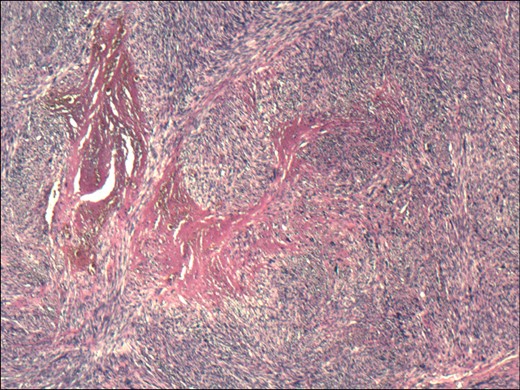

Histopathological examination revealed a 4.8 cm leiomyosarcoma of the terminal ileum (Figs2and3). The tumour involved the full thickness of the ileum. It was located 4.5 cm from the intestinal and 1.5 cm from the radial resection margin. One adjacent lymph node was retrieved, but contained no tumour cells. Immunophenotyping for CD 117 (c-kit) and DOG1 was negative and positive for desmin and caldesmon was positive. The proliferation index Ki67 was 60%. Following a multidisciplinary team meeting, no adjuvant therapy was indicated and the patient remains without evidence of disease 12 months since initial presentation.

Haematoxylin and eosin stained section showing a spindle-celled tumour with pleomorphic nuclei and pronounced mitotic activity.